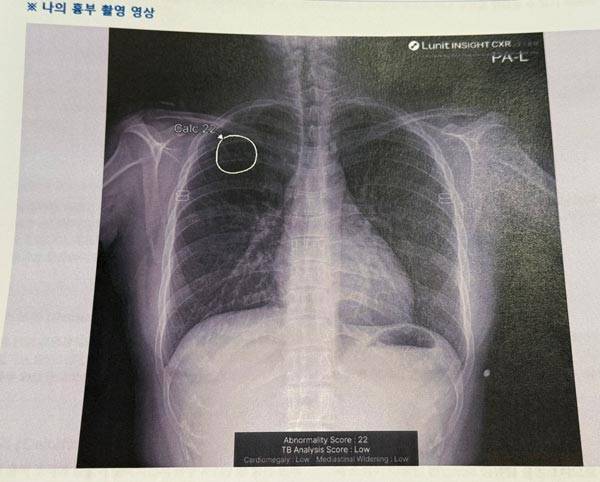

체크버스는 인공지능(AI) 기반 흉부 엑스레이 촬영과 AI 판독 리포트를 현장에서 제공하는 이동형 검진 시스템이다.

24일, 기자가 직접 코엑스 동문 광장에 설치된 '폐 건강 체크버스'에서 직접 검사를 받아봤다.